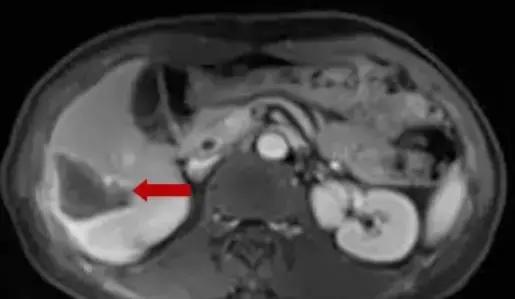

术后50天复查CE-MR,肝转移瘤消融后病灶未见明显活性。